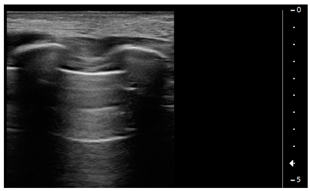

We used the following definitions to characterize the LUS patterns [15]:

- A-lines: normal appearance of horizontal, equidistant, parallel artefacts originating at regular intervals from the pleural line (visceral and parietal pleura)

- B-lines: laser-like signals arising from the hyper-echoic pleural line, extending to the bottom of the screen without fading and moving synchronously with respiration

- Subpleural consolidation: Small, triangular, or oval shaped, echo-poor region adjacent to the pleura without a tissue-like pattern (AB)

- Lobar consolidation: Large, hypoechogenic region adjacent to the pleura with a tissue-like pattern (AB) and an irregular pleural border

- Pleural effusion: Anechoic or hypoechoic collection external to lung parenchyma, typically in a dependent lung region with or without respiratory movement of the lung within the effusion (flapping lung)

Using the mentioned LUS semeiotics, lung aeration and lung pattern were classified following a 5 point score:

- Normal lung sliding, regular pleural line, and A lines

- Vertical artifacts, pleural line indented with several B-lines per field in the posterior regions

- Vertical artifacts, pleural line indented with several B-lines per field in all regions

- Broken pleural line with subpleural consolidations < 1 cm

- Consolidations > 1 cm with or without pleural effusion (Table 1).